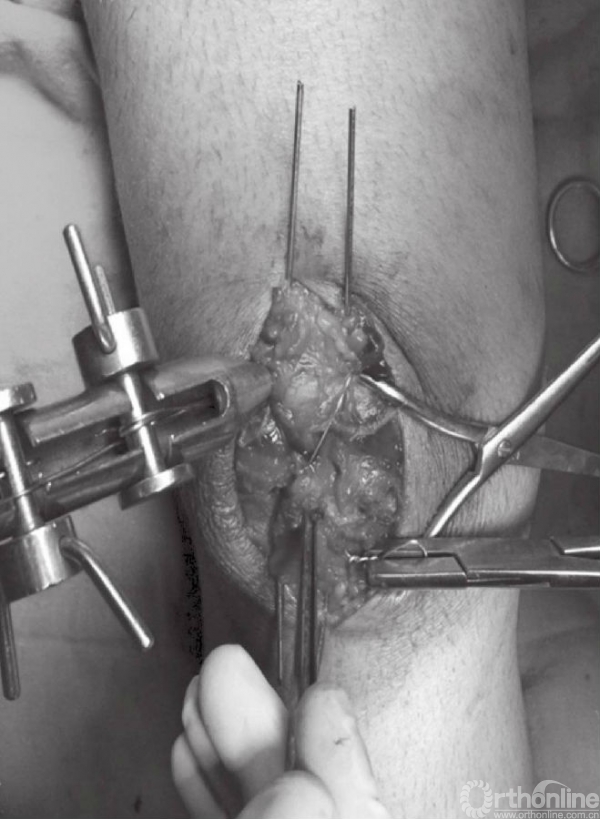

骨折端固定可采用1.6mm克氏针或者4.0mm空心螺钉。可在髌骨的中心部位,离髌骨前侧5~8mm处拧入2根克氏针或者2枚空心螺钉。也可采用克氏针以倒打的方式先穿过近端骨折块,在复位后再穿过远端骨折块(图7~10)。

图7 A~C以逆行打入的方式在骨折近端置入克氏针,离髌骨前侧约5mm

图8 置入的两枚的克氏针应保持平行,位置约为髌骨的大致1/3及2/3位置